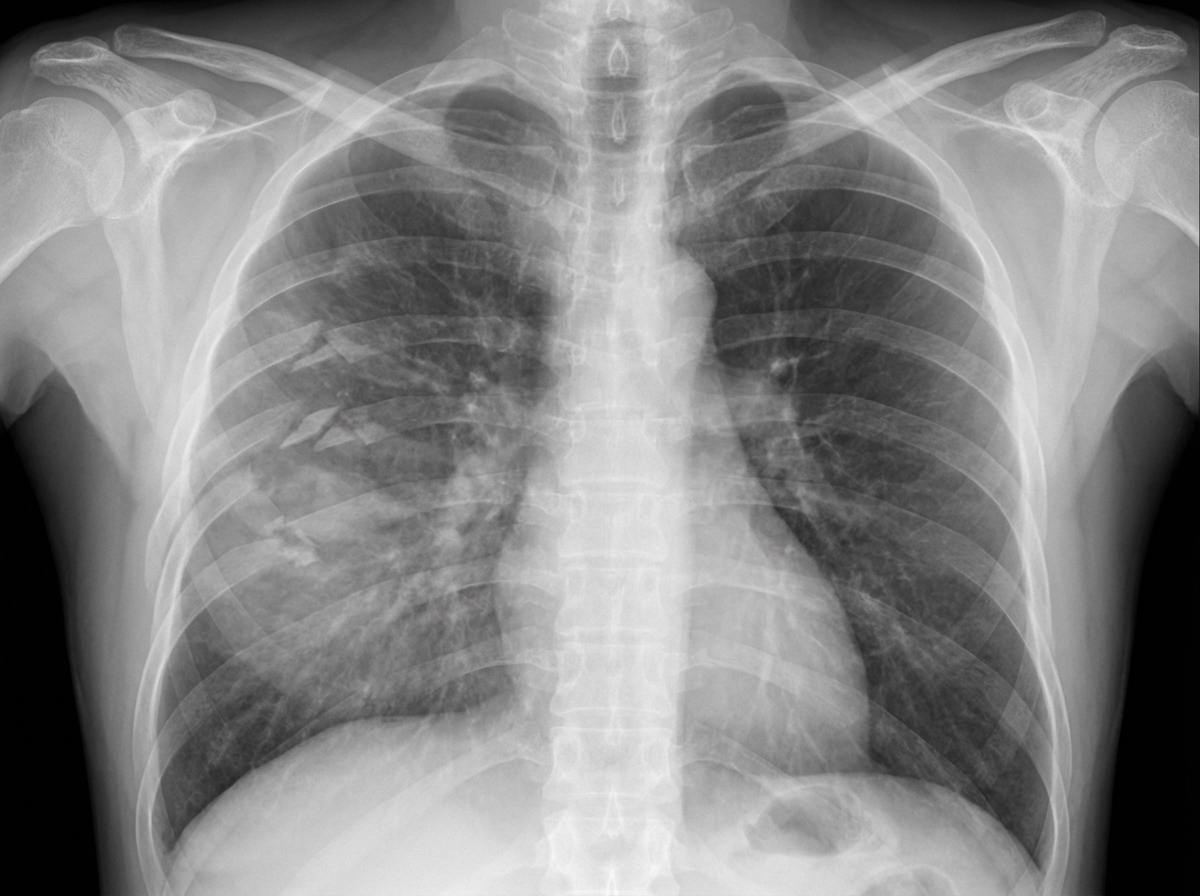

- Anterolateral thoracotomy in the 4th or 5th intercostal space (inframammary crease).

- Incision: Left anterolateral thoracotomy in the 5th intercostal space (ICS), from sternum to posterior axillary line.